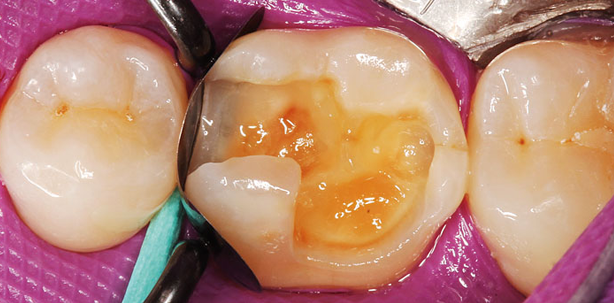

Der 48-jährige Patient wurde vor sechs Monaten mit der Biodentine-Füllung (Septodont) an Zahn 15 versorgt (Abb. 1). Die Interimsfüllung sollte nun gegen eine definitive ausgetauscht werden. Die Nachexkavation der sehr tiefen okklusal-mesialen Kavität war problemlos möglich, eine Pulpaeröffnung konnte durch dieses zweizeitige Vorgehen vermieden werden. Die Abbildung 2 zeigt die mit der Polydentia LumiContrast-Teilmatrize in Kombination mit dem dazugehörigen Spannring einfach dargestellte Kavität unter Kofferdamisolierung. Die äußerst stabile und somit „knitterfreie“ Teilmatrize ließ sich einfach durch die Kontaktbereiche manipulieren und in Position bringen. Ein Vorteil dieses Matrizensystems ist die nahezu schwarze Farbe, die durch ein spezielles Einfärbeverfahren (keine Beschichtung!) der Metallträgerfolie erreicht wurde. Somit ergibt sich ein hervorragender Kontrast im Übergang zur Zahnhartsubstanz. Dies erleichtert die Kontrolle der zervikalen Abdichtung enorm, da keinerlei Spiegelungen in Metallfolien stören und eventuell eine perfekte Randabdichtung lediglich vortäuschen. Zervikal kam zur Abdichtung ein klassischer Holzkeil zur Anwendung. Der LumiContrast-Spannring kann in zwei Varianten verwendet werden: Zum einen so wie in der Abbildung zu sehen, entsprechend einem klassischen Garrison Silver-Spannring. Es besteht aber zusätzlich die Möglichkeit, kleine dreiecksförmige Silikonhülsen aufzustecken, die eine bessere approximale Abdichtung der Flanken ermöglichen, da sie die Teilmatrizenfolien besser an die Flanken der approximalen Präparationsflächen drücken. Dies war im vorliegenden Fall allerdings nicht erforderlich. Die Abbildung 3 zeigt

die mit Phosphorsäuregel konditionierte Kavität, die Abbildung 4 die mit einem klassischen Mehrflaschenadhäsiv (OptiBond FL, Kerr) versiegelte Klebefläche. Die Restauration wurde mit einem Nanohybridkomposit (Venus Diamond A3, Heraeus Kulzer) in schräg-diagonaler Schichttechnik aufgebaut, ausgearbeitet und poliert (Abb. 5). Die Abbildung 6 zeigt denselben Zahn bei einem weiteren Kontrolltermin nach einem Jahr.